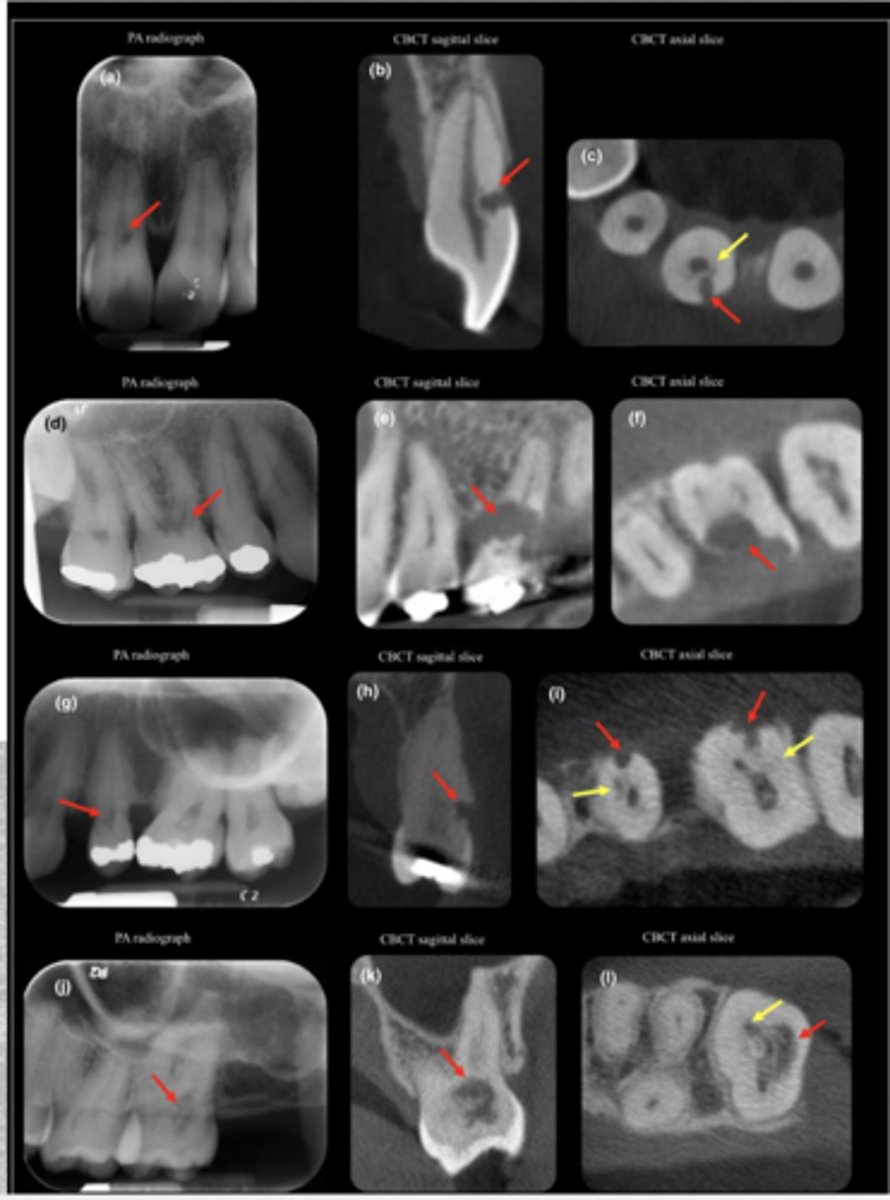

ID the problem:

- Ballooning out of root canal

internal resorption

How can you confirm if a root has internal resorption?

Take a few different angles

external resorption